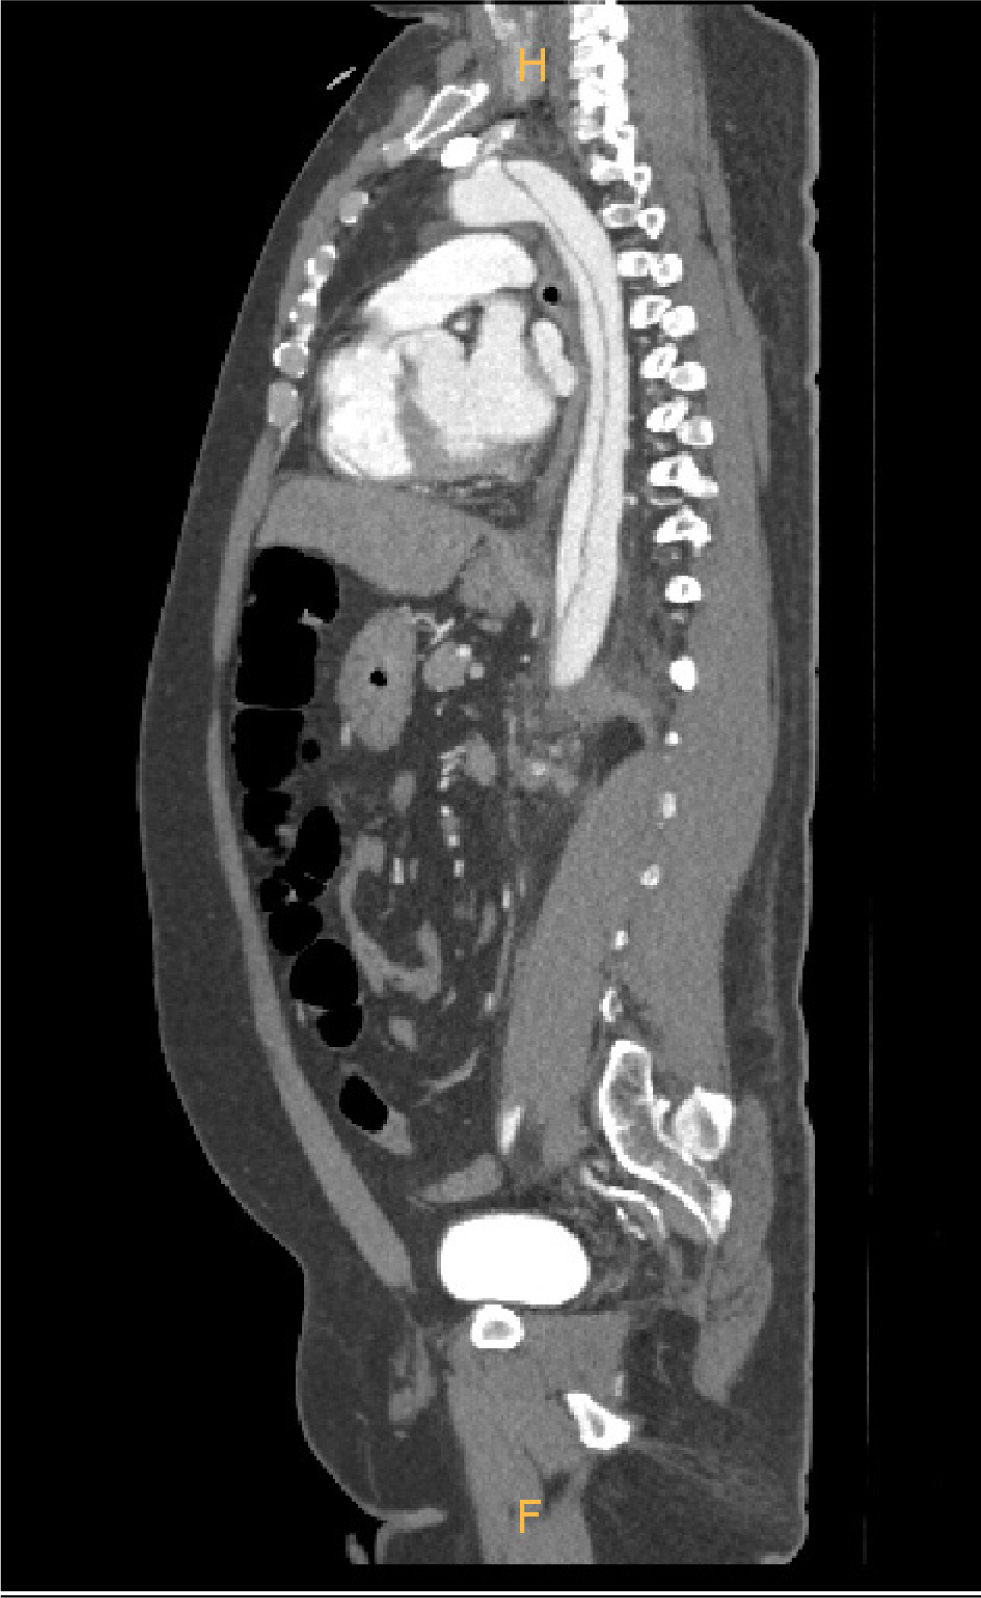

A 40-year-old male (140kg, 165cm) patient was transferred to our emergency room with chest pain. He had hypertension, coronary artery disease, and bronchial asthma that were not treated. He visited the pulmonology department with exertional dyspnea one year before surgery. On pulmonary function test, he had mild obstructive airway disease and allergen skin prick test revealed bronchial asthma to specific allergen. On chest X-ray, there was no abnormal finding (Figure 1). Contrast-enhanced computed tomography scan revealed Stanford type B aortic dissection from descending thoracic aorta to iliac arteries (Figure 2). Despite medical treatment with labetalol (120mg/h) and nicardipine (2.5mg/h), lower limb ischaemia and acute renal failure developed due to malperfusion at HAD #2 (Figure 3). Urgent surgical intervention was needed. Thoracic endovascular aortic repair (TEVAR) followed. Before transferring him to the operating room, 0.2mg glycopyrrolate was injected intramuscularly. For anaesthetic induction, 2% propofol and remifentanyl were used. The patient was paralyzed with 50mg rocuronium. Anaesthesiologist had a difficult time in endotracheal intubation with poor laryngoscopic view. After endotracheal intubation, expiratory tidal volume was 100ml with high inspiratory airway pressure (70cmH2O). On arterial blood gas analysis after 100% oxygen inhalation, severe hypoxemia and respiratory acidosis were found (pH 7.198, PCO2 61.8mmHg, PaO2 26.4mmHg, O2 Saturation 36.1%). The anaesthesiologist performed flexible bronchoscopy. There was no endotracheal or endobronchial obstruction. Severe bronchospastic asphyxia was suspected and epinephrine 0.5 mg was given subcutaneously. Then 0.5ml albuterol of 0.5% formulation was inhaled into the endotracheal tube. Methylprednisolone (1mg/Kg) was also given intravenously. After conventional therapy for severe bronchospasm, his hypoxemia and respiratory acidosis were slightly improved (pH 7.264, PCO2 56.7mmHg, PaO2 43.2mmHg, O2 Saturation 71.3%). However, his blood pressure dropped down (systolic blood pressure<70mmHg) and bradycardia (40/min) developed. Conventional therapy was ineffective for him and cardiac arrest caused by persistent hypoxemia was impending. At 12 minutes after bronchospastic attack, emergent venovenous extracorporeal life support (VV ECLS) was initiated. A 21 French drainage cannula (Bio-Medicus™ Multi-Stage Femoral Venous Cannula, Medtronic, Minneapolis, MN, USA) was inserted into the right common femoral vein and advanced into right atrium. A 17 French return cannula (Bio-Medicus™Femoral Arterial Cannula, Medtronic, Minneapolis, MN, USA) was placed at the left external iliac vein. The anaesthesiologist already inserted central venous catheter into the right internal jugular vein. Only both groins were cleansed and draped for TEVAR. Therefore, we planned secondary cannulation via the right internal jugular vein if needed after emergency VV ECLS via femoral venous cannulation. All procedures were done percutaneously with fluoroscopic guidance (Figure 4). Quadrox oxygenator and rotaflow pump (Maquet, Hirrlingen, Germany) were connected to extracorporeal circuit. Extracorporeal circulatory blood flow rate was 4.5L/min. Peripheral O2 saturation raised up to 80%. He was stabilized haemodynamically. We changed the mode of mechanical ventilation from volume controlled to pressure controlled ventilation. Limitation of inspiratory airway pressure was 40cmH2O. Expiratory tidal volume was less than 70ml. After VV ECLS, hypoxemia and hypercarbia were improved on arterial blood gas analysis (pH 7.305, PCO2 49.6mmHg, PaO2 56.2 mmHg, O2 Saturation 86.2%). Intimal tearing portion of thoracic aorta was sealed with stent graft (Valiant thoracic stent graft with the Captiva delivery system, Medtronic) on VV ECLS. The patient was transferred to intensive care unit after surgery without any problem. Bronchodilator was used for inhalation every 4 hours. After 12 hours after VV ECLS, his expiratory tidal volume was increased up to 450ml with appropriate inspiratory airway pressure (less than 40cmH2O). VV ECLS was weaned at POD#1 and decannulation was done without haemorrhagic complication. Patient could be weaned from mechanical ventilator and extubated at POD#2. He could be discharged at POD#7 without any respiratory or cognitive dysfunction. Malperfusions of left kidney and left iliac artery were resolved and there was no abnormal finding of lung parenchyma and pulmonary vessels on contrast-enhanced computed tomography scan at POD#14 (Figure 5). The patient has been treated with a bronchodilator at the Pulmonology Department. He has no more episode of bronchospastic asphyxia.

Contrast-enhanced computed tomography scan showing Stanford type B aortic dissection.